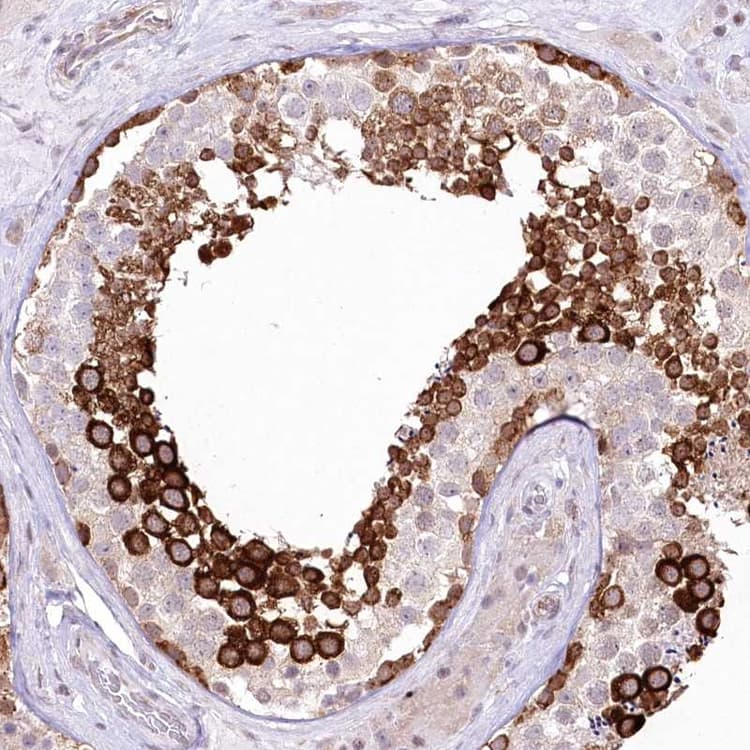

Anti-DBPA antibody(ab251828)

Rabbit Polyclonal DBPA antibody. Suitable for IHC-P, ICC/IF and reacts with Human samples. Immunogen corresponding to Recombinant Fragment Protein within Human YBX3 aa 200-300.

Applications ICC/IF, IHC-P

Species Reactivity Human